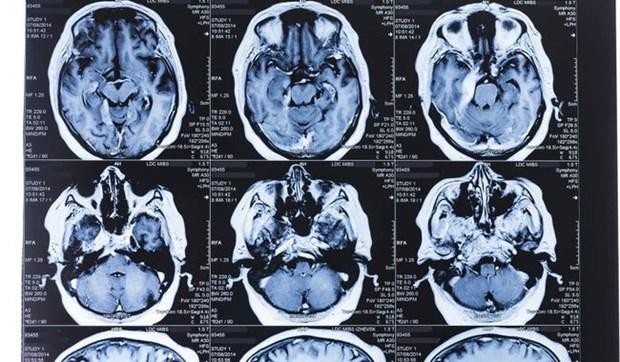

Các nhà nghiên cứu đã phát hiện sự khác biệt rõ rệt về “chất xám” giữa những người từng mắc COVID-19 và những người chưa mắc. (Nguồn: Getty Images)

Các nhà nghiên cứu đã phát hiện sự khác biệt rõ rệt về “chất xám” - các tế bào thần kinh xử lý thông tin trong não - giữa những người từng mắc COVID-19 và những người chưa mắc.

Cụ thể, “chất xám” ở thùy trán và thùy thái dương đã bị mỏng đi ở nhóm mắc COVID-19, khác với tình trạng bình thường ở nhóm không mắc COVID-19.

Với người bình thường, sự thay đổi về khối lượng hoặc độ dày của “chất xám” cũng diễn ra theo thời gian khi con người già đi. Nhưng trong nghiên cứu này, sự biến đổi ở những người mắc COVID-19 diễn ra mạnh hơn.

Đáng lưu ý, nhóm nghiên cứu đã tách những bệnh nhân COVID-19 phải nhập viện thành một nhóm riêng và phát hiện sự thay đổi của “chất xám” cũng tương đương với những bệnh nhân thể nhẹ. Điều này cho thấy người mắc COVID-19 dù nhẹ cũng có biểu hiện não bộ suy giảm về khối lượng.